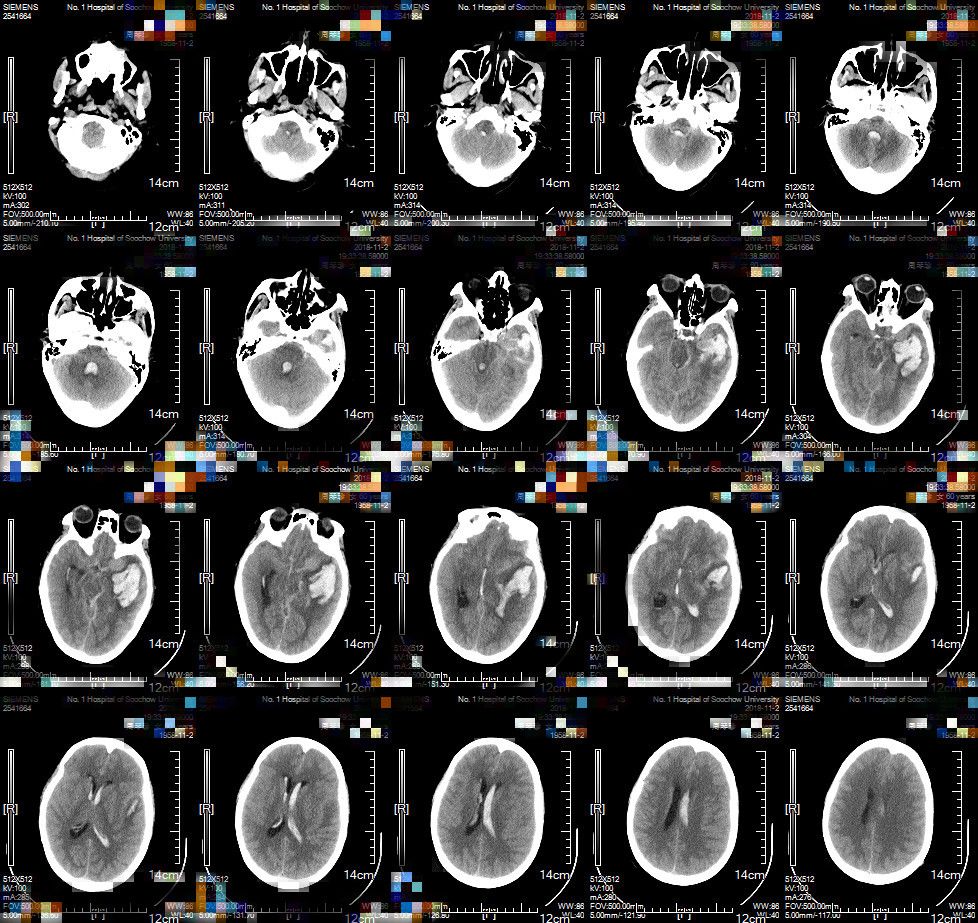

术后继续脱水,抗炎及预防性抗癫痫等治疗。术后复查CT,显示动静脉瘘及扩张血管切除,左侧颞叶血肿清除。侧脑室、三脑室、四脑室血肿残存,中线结构居中(图4)。

图4. 术后头部CT:动静脉瘘及瘤样扩张均切除,左侧颞叶血肿清除,残存侧脑室、三脑室、四脑室血肿,中线结构居中。